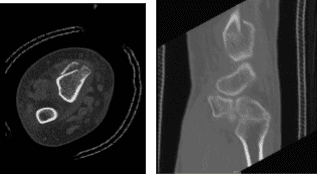

El paciente presentó resultados para la tomografía computarizada que mostraron fractura intraarticular aguda a subaguda del radio distal derecho como se detalló anteriormente. Fractura compañera del estiloides cubital como se indicó. Pequeños derrames articulares. Condrocalcinosis como se ha detallado arriba.

TAC muñeca derecha sin contraste